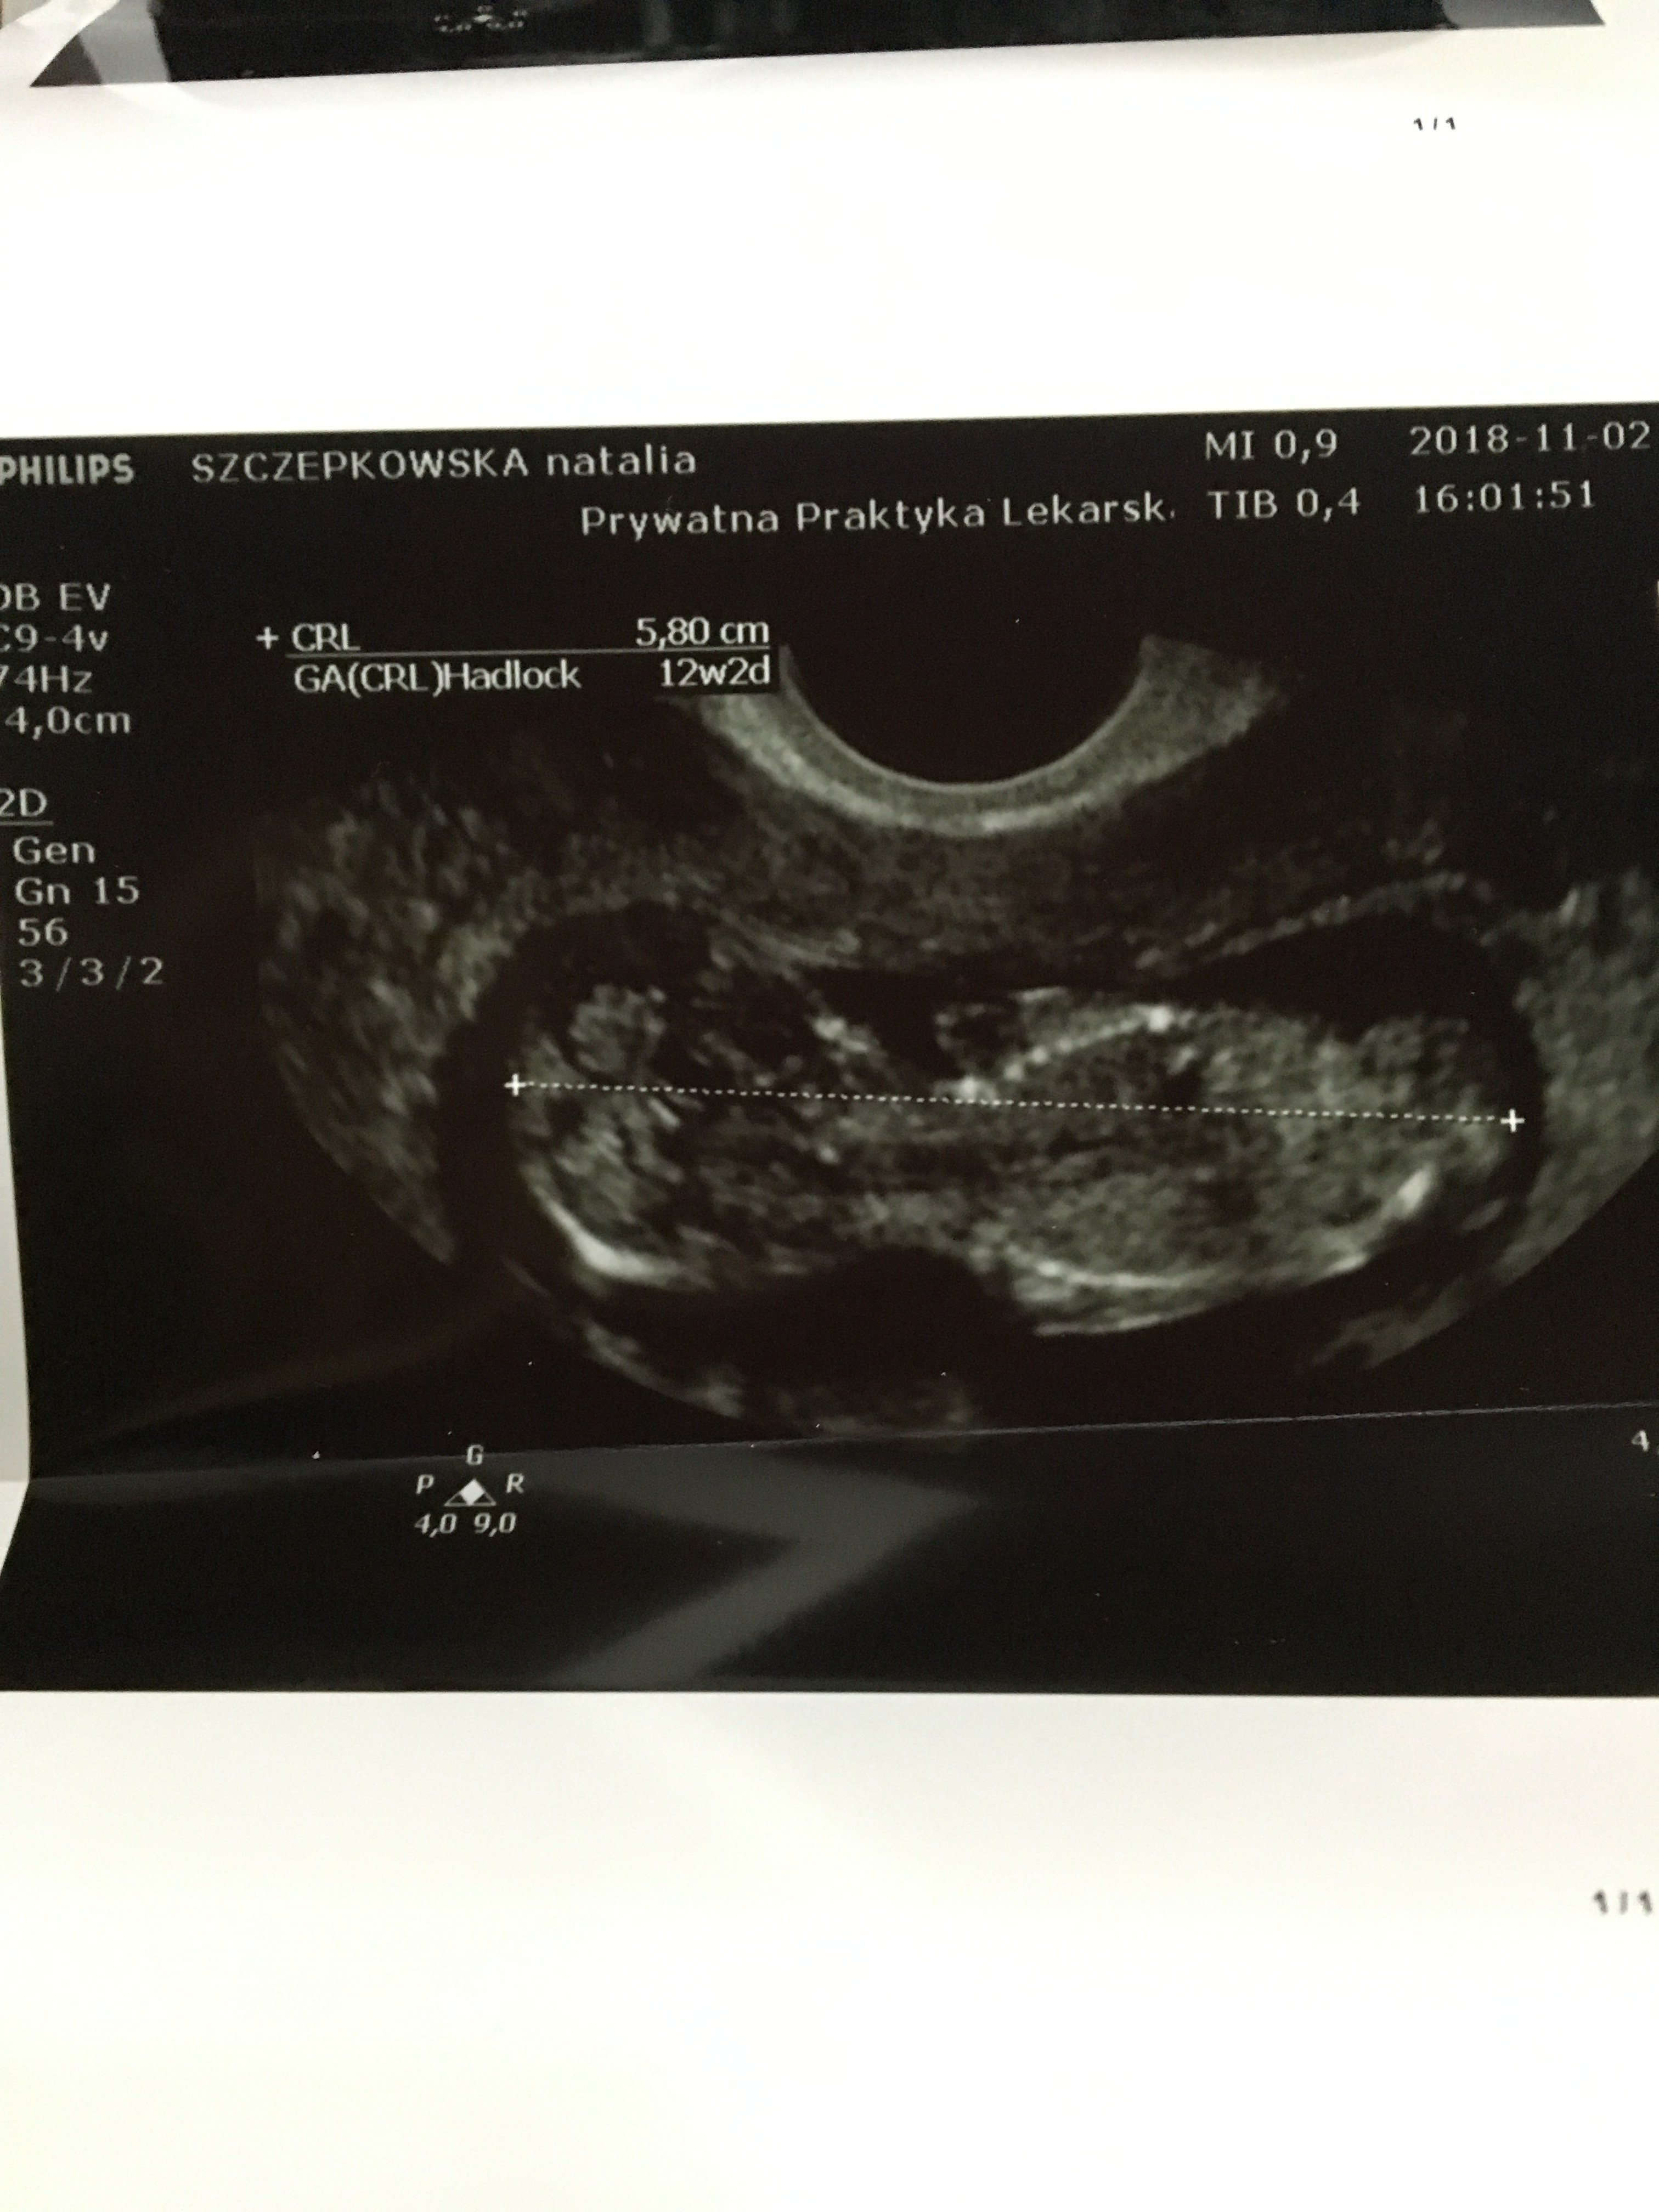

Witam w 19 tygodniu ciąży dowiedziałam się ze będę miała dziewczynkę w 20 tyg okazało się jednak , że to chłopak. Sama już nie wiem bo na jednym usg widać na pewno dziewuche a na drugim chłopca. Może to pempowina ?? Może ktoś mi pomoże rozwiązać ta zagadkę

no nic , zobaczymy na kolejnym USG. To doswiadczona Pani wiec chyba wie co mówi a ja ogladam zdjęcia pod każdym kątem i szukam śladów kobiecych